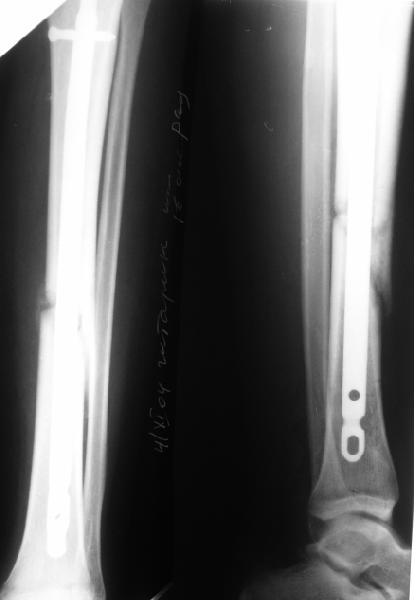

Просьба простить за длительное молчание, не было фотоаппарата, чтобы перенести рентгенограммы. Больного прооперировали в прошлый четверг, как и предполагали, голень проблем не доставила(настолько, что даже не ввели дистальные винты по ряду причин: срок после травмы, целая малоберцовая, последующая длительная ходьба без нагрузки, да и гвоздь сел плотно). Изначально планировали после удаления фиксатора антеградно завести стержень и утопить конец, но вопрос был исчерпан, когда выяснилось, что все имеющиеся стержни слишком длинные, пришлось ретроградно забить большеберцовый гвоздь, после рассверливания; серьезные проблемы возникли с устранением ротации. В вертельной области сломали стержень-джойстик(привет установщику эндопротеза), дальнейшие манипуляции проводили пучком спиц и стержнем с кондуктором. Закончили все аппаратом таз-бедро. Решили что возможные огрехи с ротацией устраним после открытого вправления. Снимки прилагаю. Спасибо за участие в обсуждении. Обязуюсь информировать о дальнейших этапах лечения.